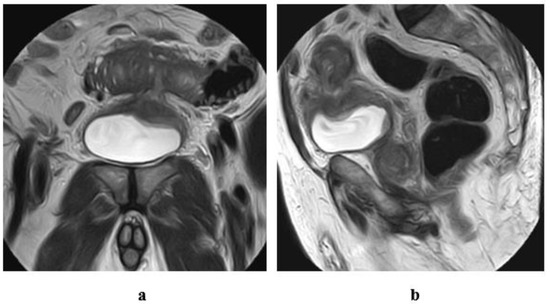

3.2. N-Staging

- Thoeny, H.C.; Froehlich, J.M.; Triantafyllou, M.; Huesler, J.; Bains, L.J.; Vermathen, P.; Fleischmann, A.; Studer, U.E. Metastases in normal-sized pelvic lymph nodes: Detection with diffusion-weighted MR imaging. Radiology 2014, 273, 125–135. [Google Scholar] [CrossRef]

- Akduman, E.I.; Momtahen, A.J.; Balci, N.C.; Mahajann, N.; Havlioglu, N.; Wolverson, M.K. Comparison between malignant and benign abdominal lymph nodes on diffusion-weighted imaging. Acad. Radiol. 2008, 15, 641–646. [Google Scholar] [CrossRef] [PubMed]